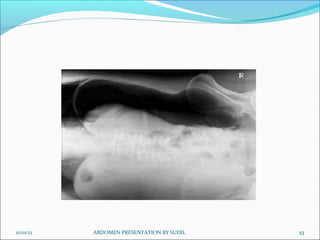

Picture criteria:

 Air fluid levels when an erect abdomen cannot be obtained.

 Lung area above dome of diaphragm

 Lateral abdominal wall and properitoneal fat

 Psoas muscle, lower border of liver and kidney shadows

 No rotation